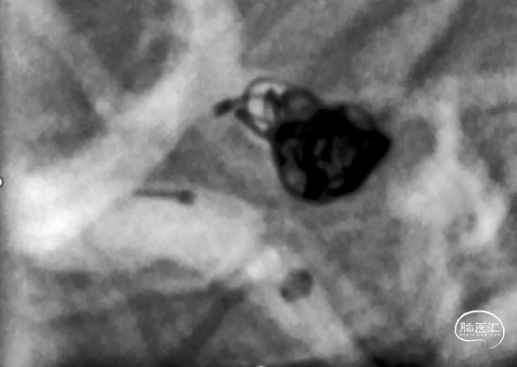

CTA

弓部造影显示双侧颈动脉、椎动脉血流通畅,右侧颈内动脉交通段可见动脉瘤。

右侧颈内动脉造影,可见后交通动脉瘤,大小约为4mm*6mm动脉瘤,瘤颈宽3.6mm。后交通血流通畅,大脑前动脉及大脑中动脉血流通畅。

造影确认工作位,瘤内可见造影剂滞留。